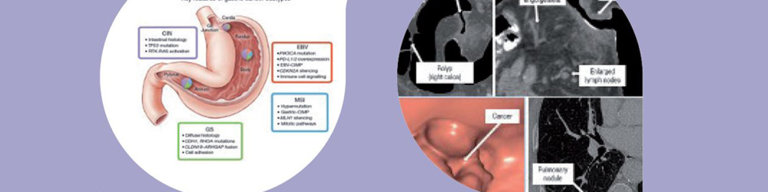

2021 EMPO临床肠道图块基本知识

胃肠道图

胃肠道图理学基础知识2后端版本化向读者介绍肠胃肿瘤领域最新发现和最新实践概念,这些概念分布广度肠胃恶性